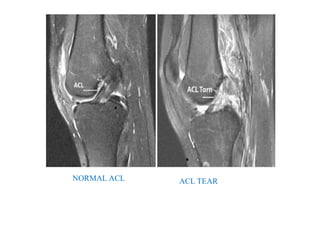

• MRI KNEE

• Best evaluated in saggital images.

• Meniscal injuries

• ACL and PCL injuries

• Collateral ligament injuries

NORMAL ACL ACL TEAR